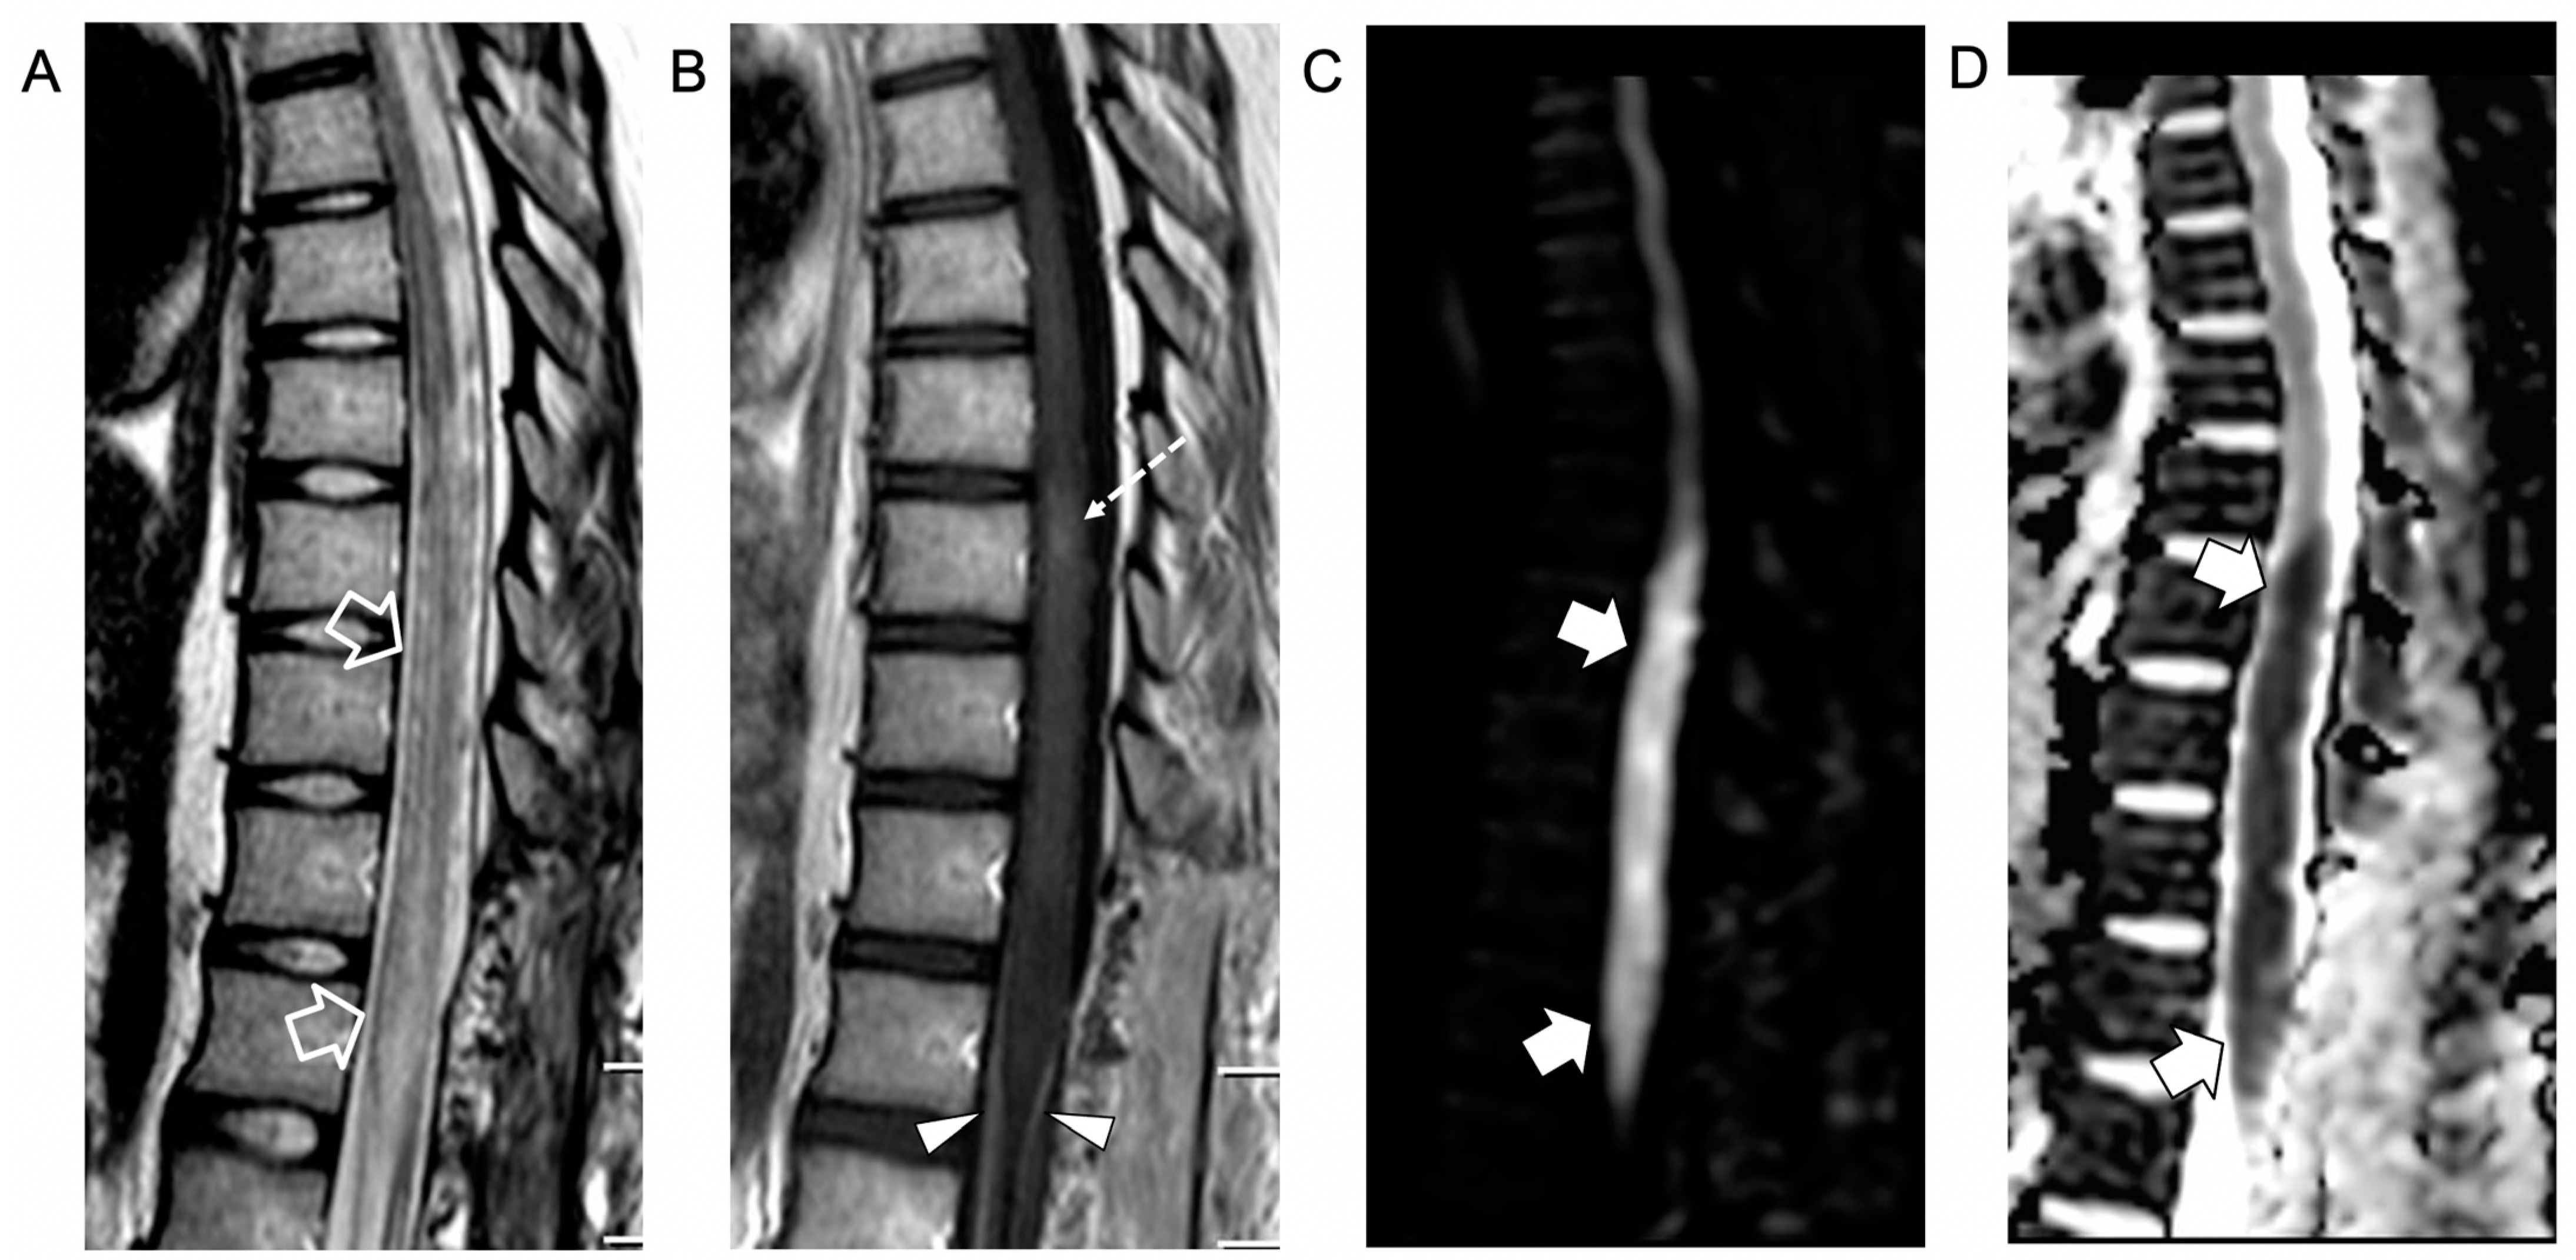

An intradural extramedullary lobulated lesion was also noted at the level of the conus medullaris, with several similar small nodular lesions spreading along the cauda equina nerve roots and conus medullaris surface (Figure 2). A brain MRI demonstrated small subcortical gliotic changes in the right temporal lobe that remained stable in follow-up studies. Chest computed tomography (CT) and whole-body MRI were negative, as well as spinal digital subtraction angiography. A new CSF examination was performed: no atypical cells were detected but immunochemical tests showed barrier damage in the absence of oligoclonal bands. New microbiological tests and PCR on CSF and blood excluded some infective etiologies, in particular the presence of Cryptococcus, Aspergillus, Mycobacterium tuberculosis, Borrelia, Yersinia, Toxoplasma, and Bartonella. Antimicrobial therapy was shifted to 600 mg teicoplanin per day, subsequently substituted with 3 g ampicillin four times a day. For the suspicion of neoplastic disease, a biopsy of the extramedullary lesion was performed, revealing an ischemic lesion with perivascular inflammatory infiltrates and phagocytosis of uncertain significance, suggestive of an unspecified infective lesion. While waiting for the histological analysis, a second infusion of immunoglobulin, oral cyclophosphamide, and steroids was started for the suspicion of SLE-related transverse myelitis. An immediate postoperative spinal MRI performed 3 weeks after the onset revealed complete removal of the intradural extramedullary mass, while the spinal cord lesion and nerve root involvement were stable. The clinical picture worsened with progressive paraplegia and anesthesia of the lower limbs, urinary incontinence, and deterioration of neurophysiological findings. During the following weeks, plasmapheresis, cyclophosphamide, and immunoglobulin were administered and ampicillin was continued. Spinal MRI performed 6 weeks after clinical onset and showed a new acute ischemic lesion involving the inferior dorsal spinal cord and conus medullaris and additional small nodular lesions along the conus medullaris surface (Figure 3).

Figure 3.

Contrast-enhanced spinal MRI performed 6 weeks after clinical onset. Sagittal T2-weighted (A), post-contrast T1-weighted (B), and diffusion-weighted (C) images with corresponding ADC map (D). The swelling and T2 signal alterations in the lower dorsal spinal cord and conus medullaris are worsened (empty arrows) with persistence of the focal intramedullary contrast enhancement (dashed arrow) and cauda equina nerve root contrast enhancement (arrowheads). Note that there is a new acute ischemic infarct at the level of the conus medullaris (thick arrows).